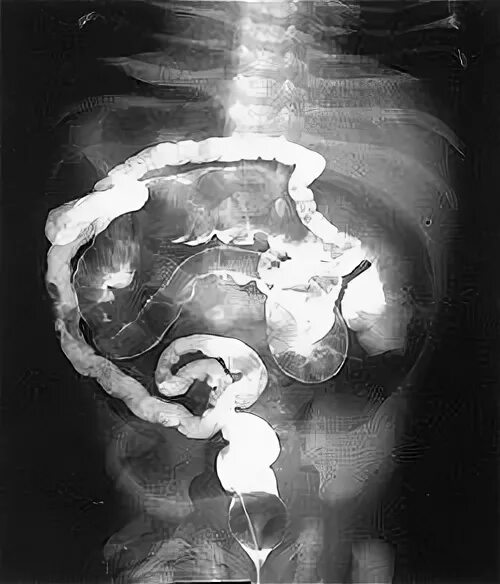

Парез кишечника операция